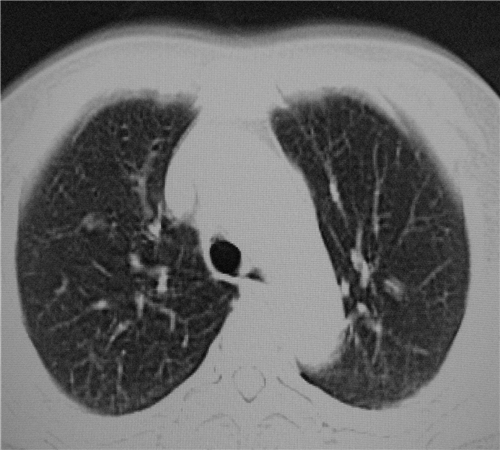

标题: CT26849:女67岁反复胸痛两天余,临床考虑夹层。 [打印本页]

标题: CT26849:女67岁反复胸痛两天余,临床考虑夹层。

右肺感染,未见夹层。

既然考虑夹层,建议强化!另:右下肺感染!

1)右肺感染性病变。2)建议行ct增强扫描或mri检查排除主动脉夹层。

双下肺感染,右侧显著。有无夹层,增强扫描后再诊断。

1. 感染性病变,2.未见夹层,3.食道未见异常。